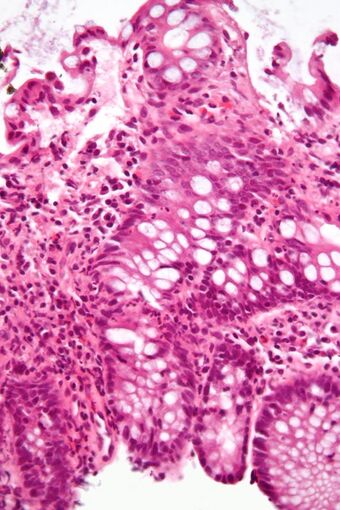

An important investigation in the assessment of colitis is biopsy. A very small piece of tissue (usually about 2mm) is removed from the bowel mucosa during endoscopy and examined under the microscope by a histopathologist. It can provide important information regarding the cause of the disease and the extent of bowel damage.[citation needed]

Micrograph showing intestinal crypt branching, a histopathological finding of chronic colitis. H&E stain.